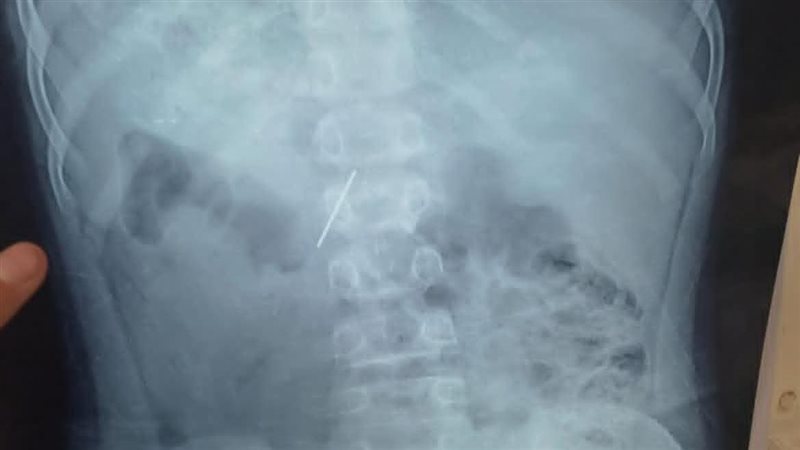

نجح قسم جراحة الأطفال بمستشفى الأطفال التخصصي في بنها، في استخراج مسمار دباسة كراسة اخترق جدار بطن طفل واستقر داخل التجويف البطني، بعد تدخّل جراحي متقدّم جمع بين المنظار وجهاز السي أرم لتحديد الموقع بدقة متناهية.

وصل الطفل إلى مستشفى الأطفال التخصصي في بنها وهو يعاني ألمًا شديدًا وقلقًا أسرته، حيث كشفت الفحوصات الأولية وجود جسم غريب حاد داخل البطن؛ إذ قرر الفريق الطبي باتخاذ الإجراءات اللازمة والحاسمة، وهو «استئصال المسمار» بأسرع وأمن بطريقة ممكنة؛ لتفادي أي مضاعفات قد تهدد حياة المريض.

وقاد الفريق الطبي بمستشفى الأطفال التخصصي في بنها، العملية بامتياز تحت إشراف الدكتور محمد متولي، رئيس قسم جراحة الأطفال، ووليد محمد، استشاري جراحة، ومحمود ممدوح، نائب قسم الجراحة، حيث تم توظيف المنظار الجراحي؛ لتقليل آثار الجراحة والشفاء السريع، فيما لعب جهاز الـ«سي أرم» دور الخريطة الحية لتحديد موقع المسمار بدقة مدهشة، ما حول العملية إلى مزيج من مهارة الجراح وذكاء الأجهزة.